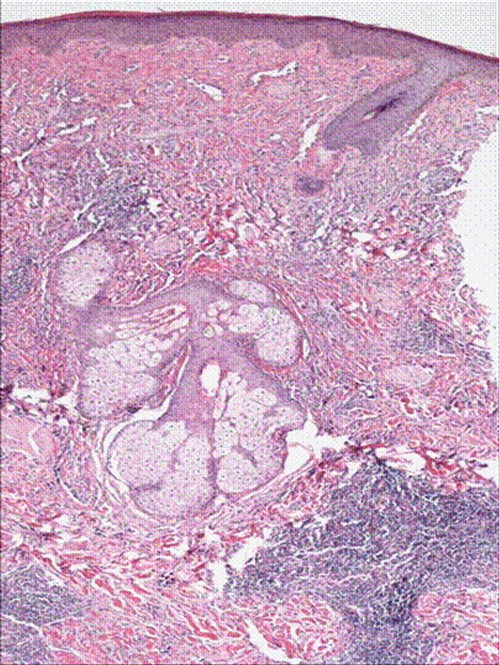

H& E stain of punch biopsy of the lesion from the cheek showing infilterating vascular tumor.